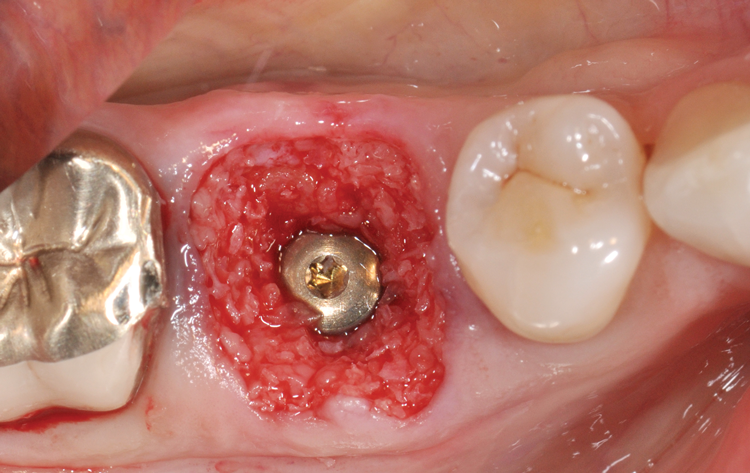

(5.) Radiographic assessment of the mandibular right first molar ridge form, including 3D evaluation of the septal/buccal, lingual, and apical bone for implant stabilization. The goal is to restoratively center the implant.

Figire 5

(7.) Restoratively centered guided osteotomy and implant insertion.

Figure 7

(8.) Restoratively centered guided osteotomy and implant insertion.

Figure 8